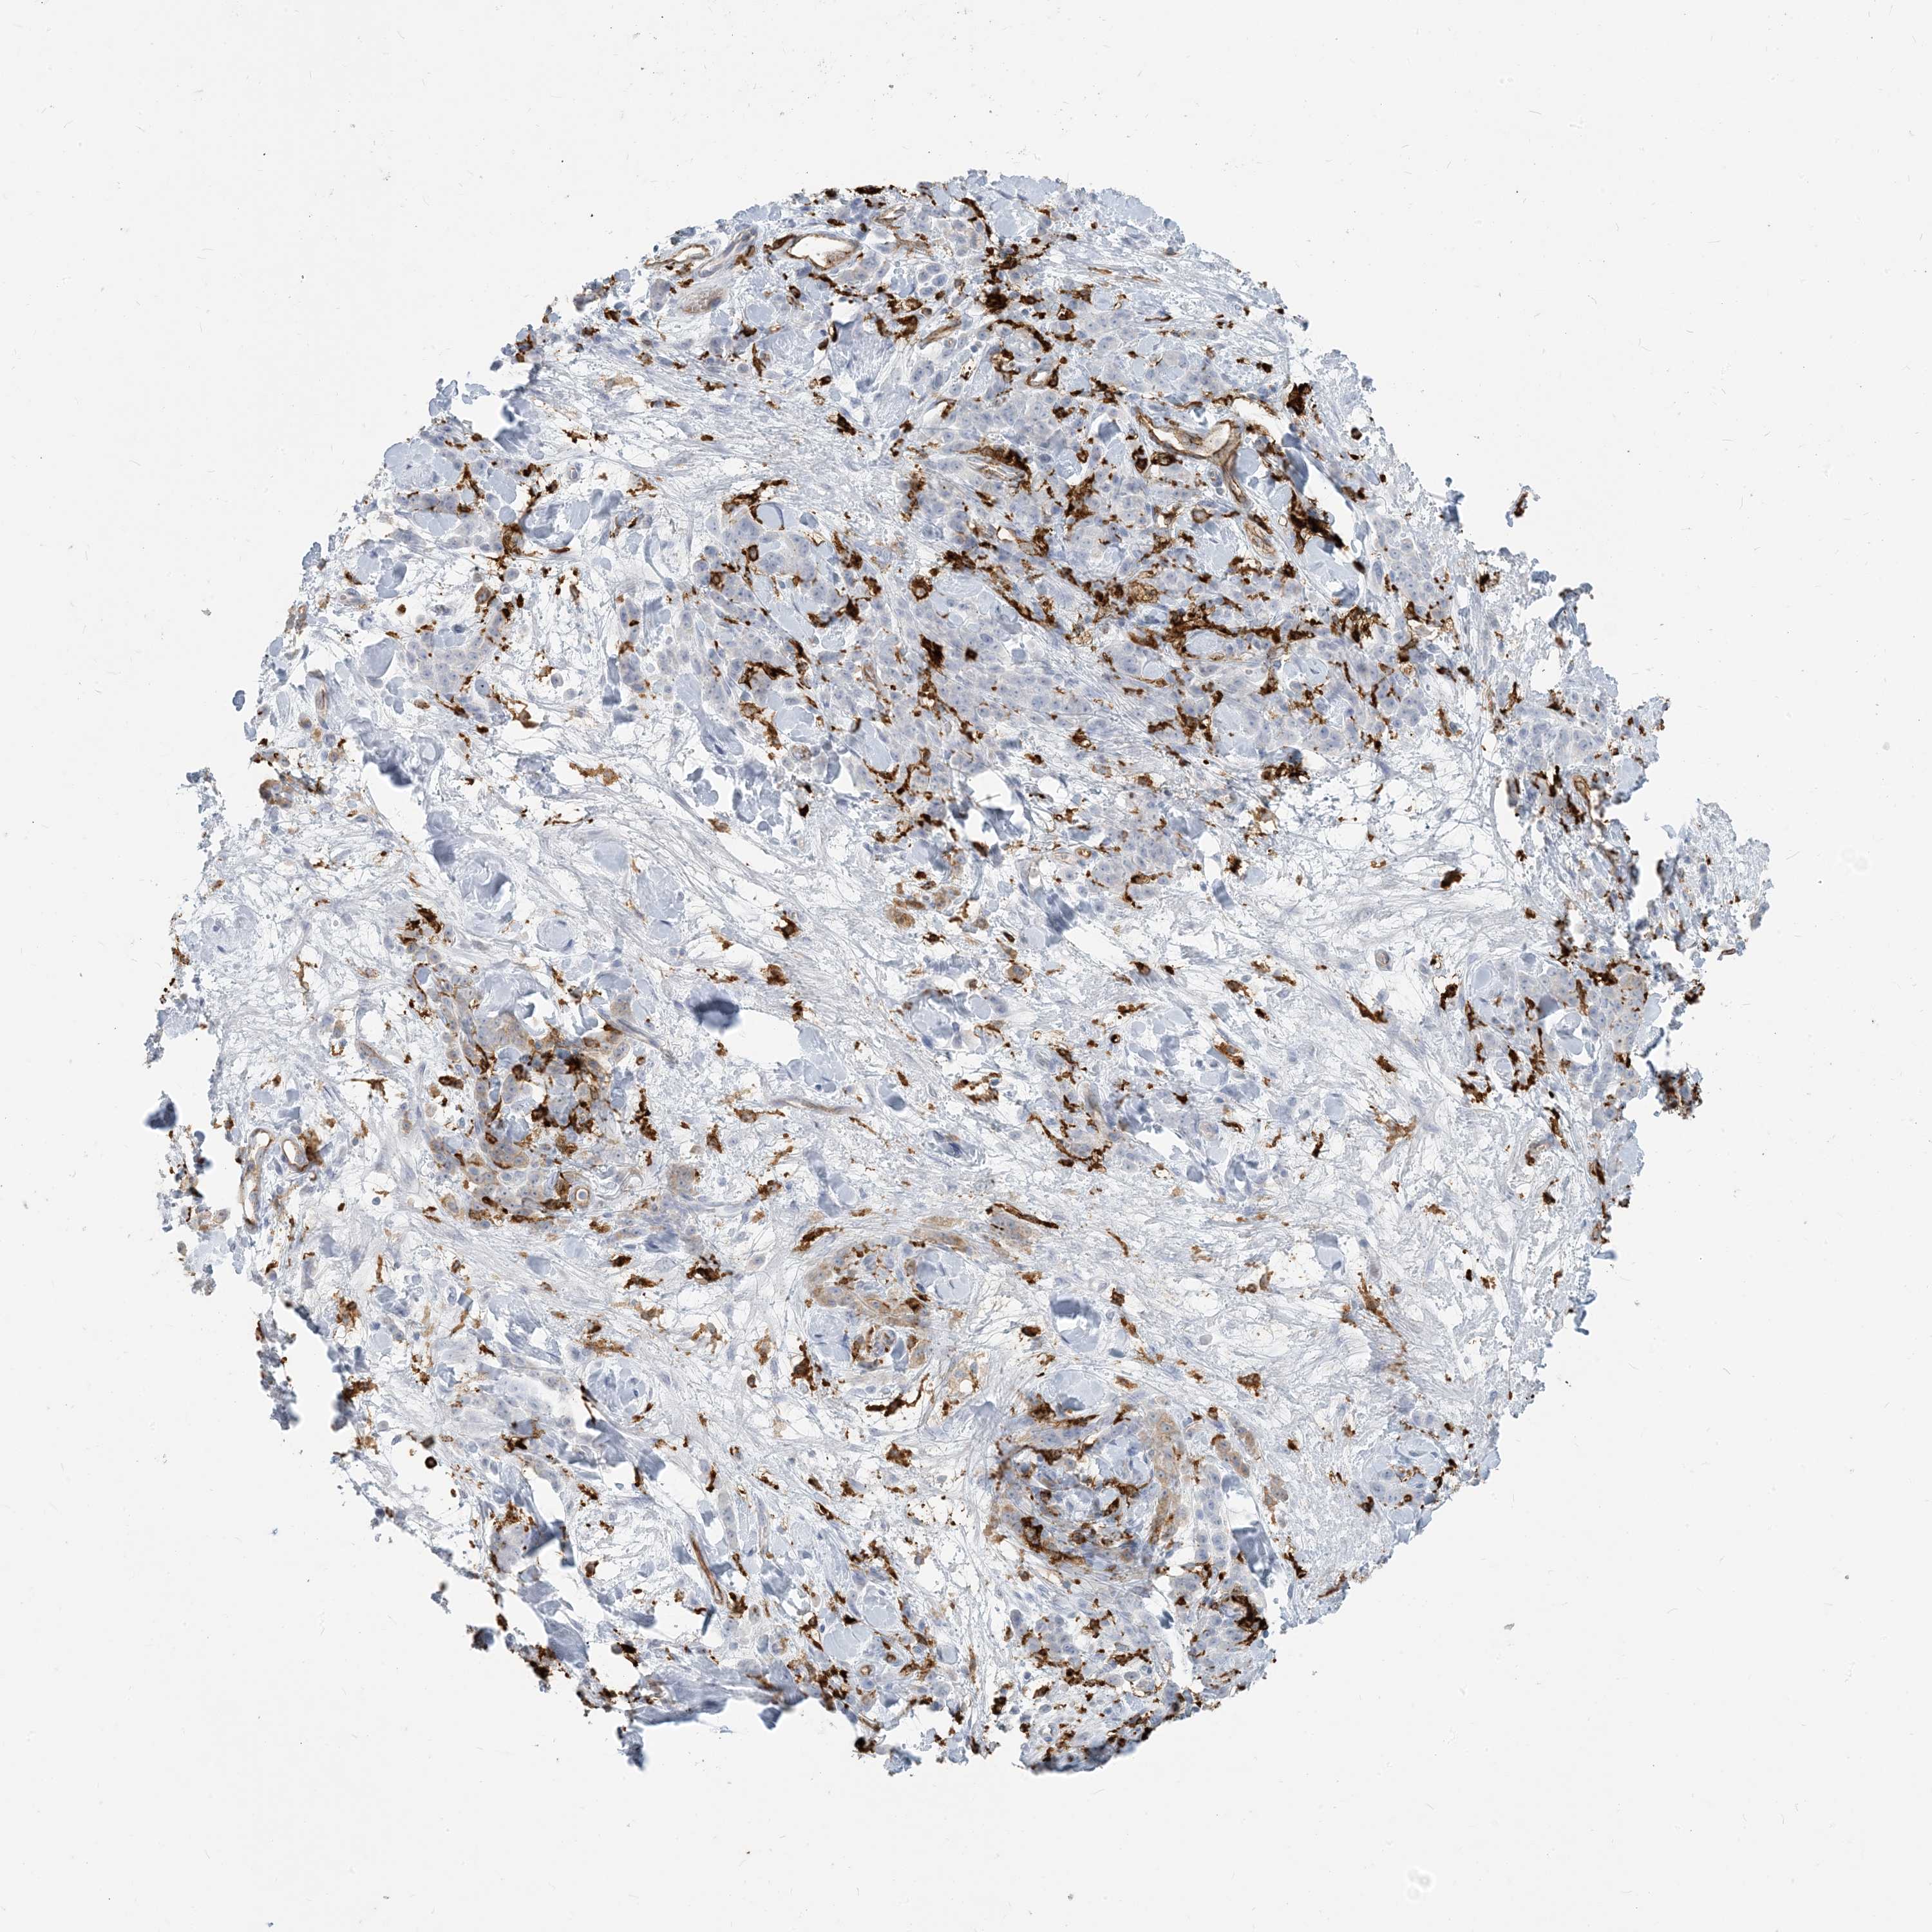

STOMACH CANCER - Protein expressioni

A mouse-over function shows sample information and annotation data. Click on an image to view it in a full screen mode. Samples can be filtered based on level of antibody staining by selecting one or several of the following categories: high, medium, low and not detected. The assay and annotation is described here.

Note that samples used for immunohistochemistry by the Human Protein Atlas do not correspond to samples in the TCGA dataset.

Antibody stainingi

Antibody staining in the annotated cell types in the current human tissue is reported as not detected, low, medium, or high, based on conventional immunohistochemistry profiling in selected tissues. This score is based on the combination of the staining intensity and fraction of stained cells.

Each image is clickable and will lead to virtual microscopy that enables deeper exploration of all samples and also displays staining intensity scores, fraction scores and subcellular localization as well as patient and tissue information for each sample.

Antibody HPA043151

Antibody CAB015400

Antibody CAB034021

Staining

High

Medium

Low

Not detected

Intensity

Strong

Moderate

Weak

Negative

Quantity

>75%

75%-25%

<25%

None

Location

Nuclear

Cytoplasmic/membranous

Cytoplasmic/membranous,nuclear

Adenocarcinoma, NOS